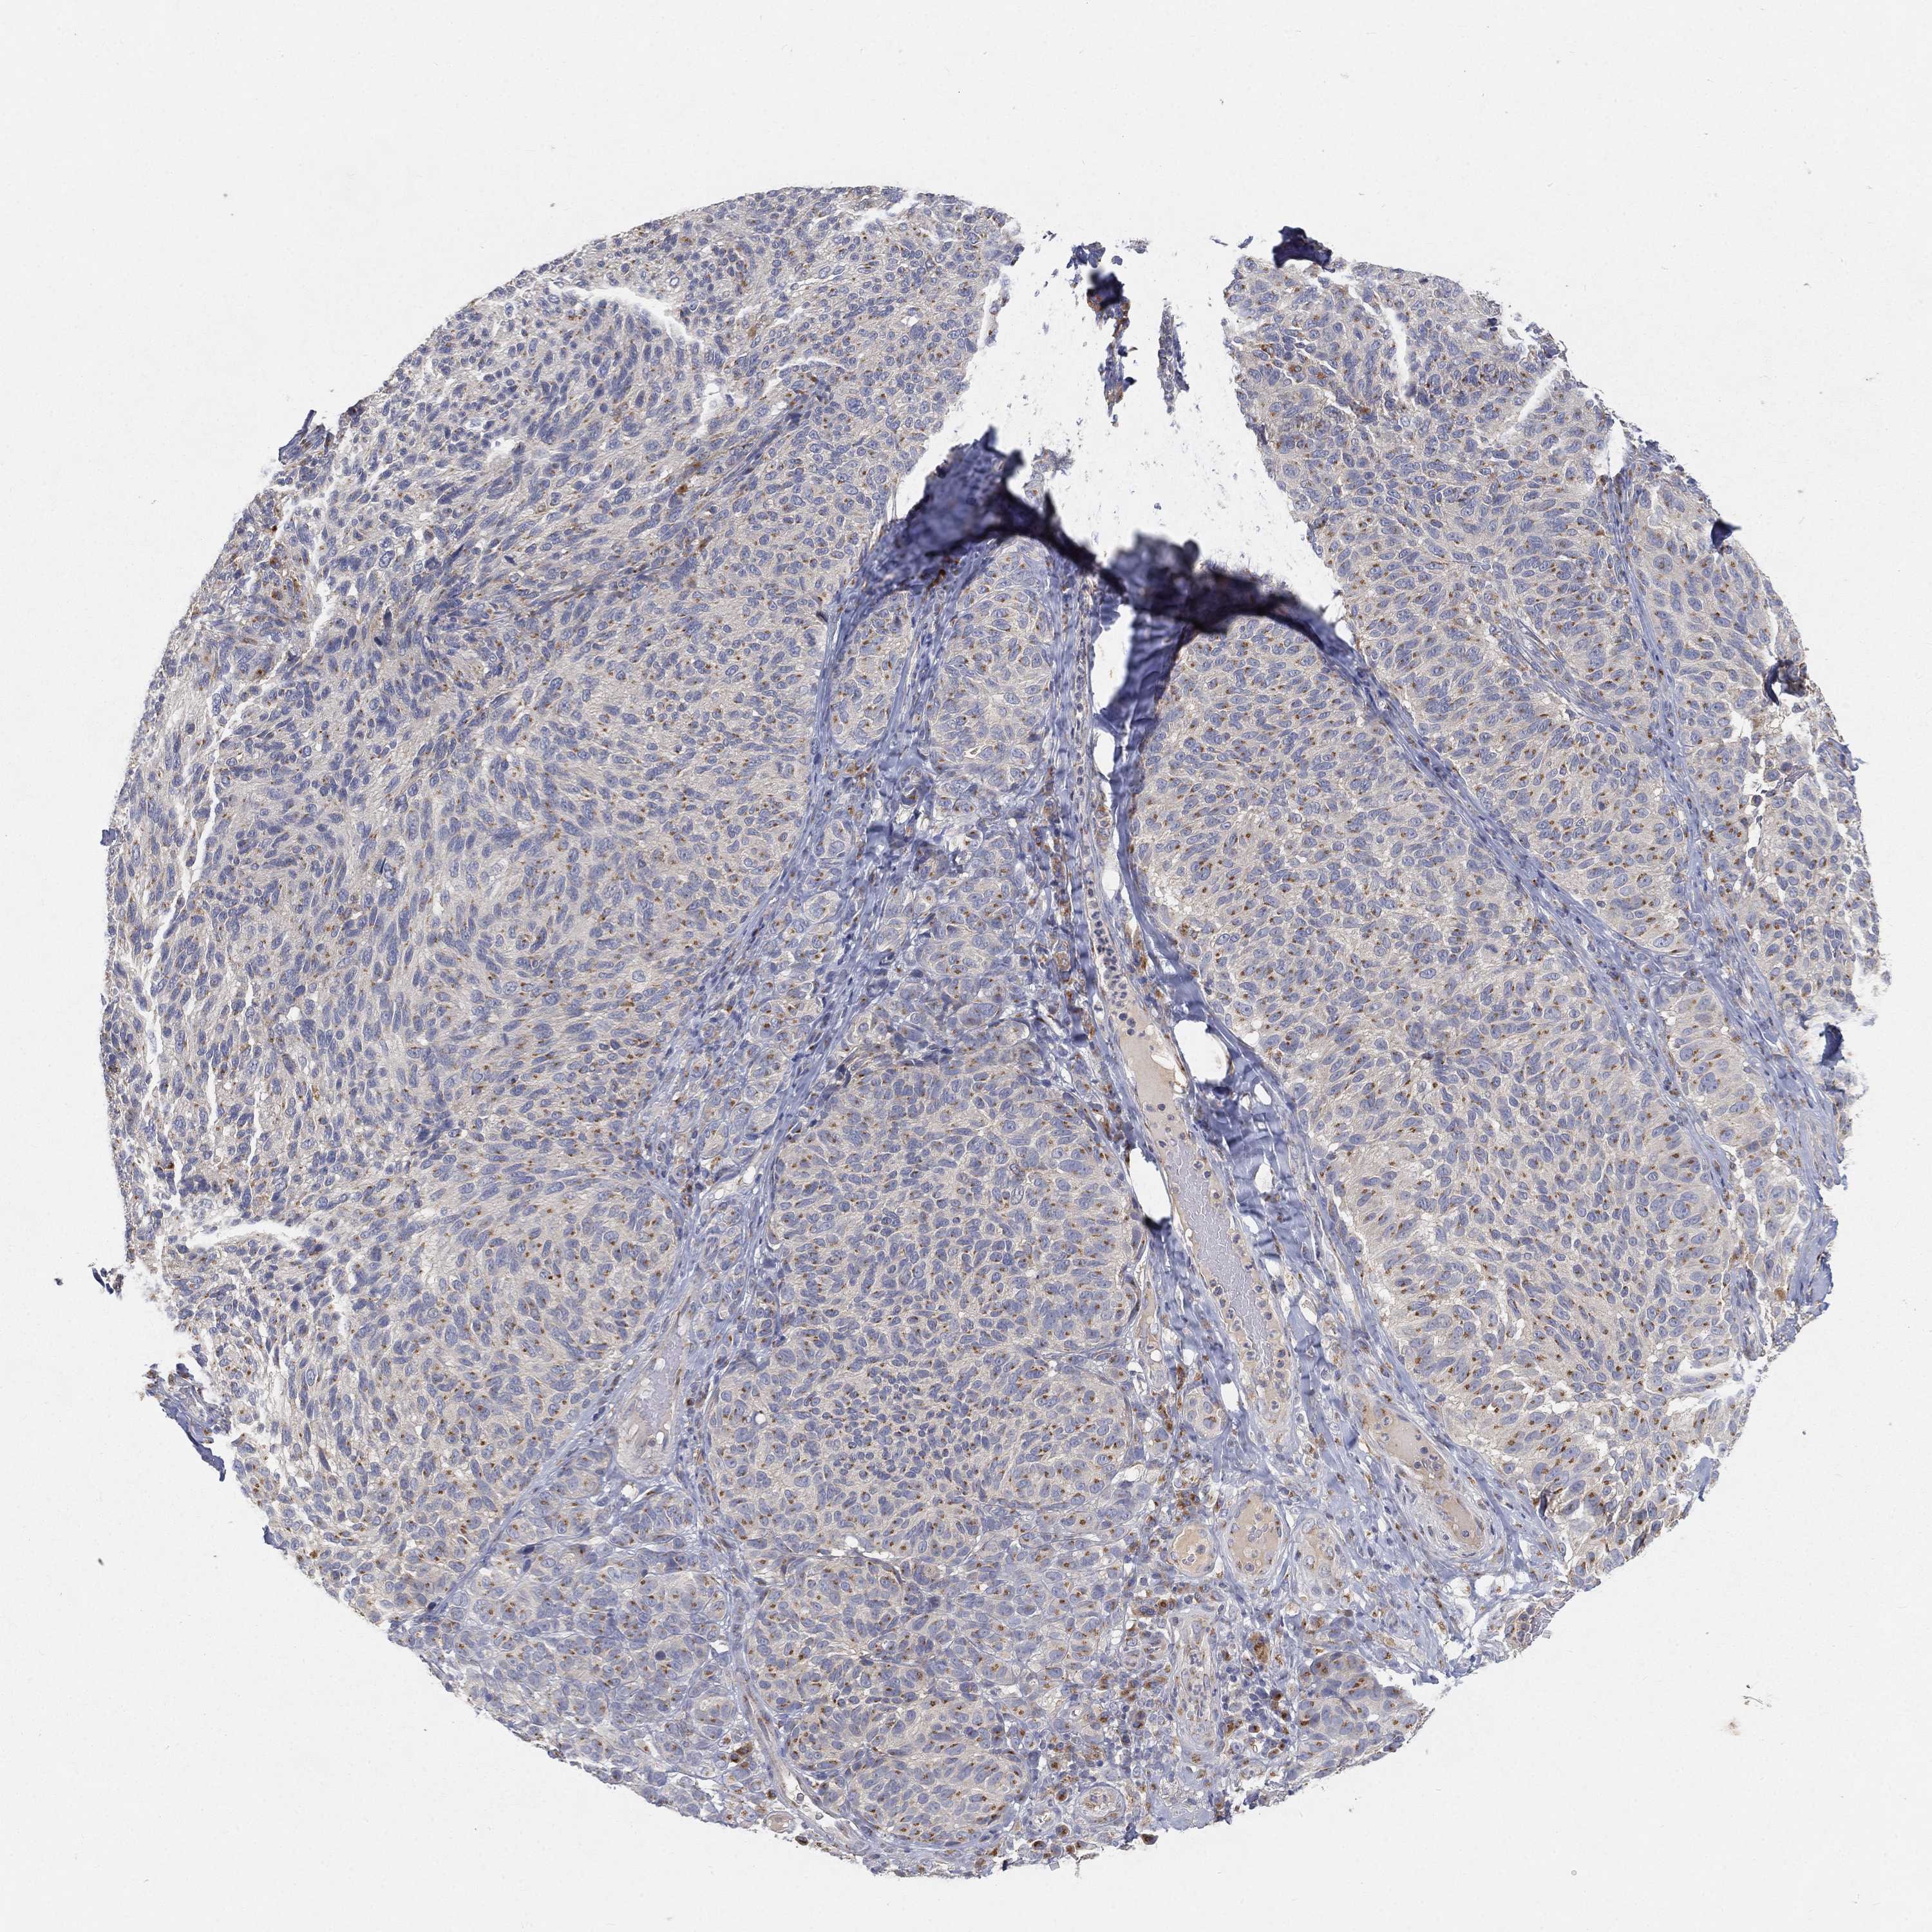

MELANOMA - Protein expressioni

A mouse-over function shows sample information and annotation data. Click on an image to view it in a full screen mode. Samples can be filtered based on level of antibody staining by selecting one or several of the following categories: high, medium, low and not detected. The assay and annotation is described here.

Note that samples used for immunohistochemistry by the Human Protein Atlas do not correspond to samples in the TCGA dataset.

Antibody stainingi

Antibody staining in the annotated cell types in the current human tissue is reported as not detected, low, medium, or high, based on conventional immunohistochemistry profiling in selected tissues. This score is based on the combination of the staining intensity and fraction of stained cells.

Each image is clickable and will lead to virtual microscopy that enables deeper exploration of all samples and also displays staining intensity scores, fraction scores and subcellular localization as well as patient and tissue information for each sample.

Antibody HPA070413

Staining

High

Medium

Low

Not detected

Intensity

Strong

Moderate

Weak

Negative

Quantity

>75%

75%-25%

<25%

None

Location

Nuclear

Cytoplasmic/membranous

Cytoplasmic/membranous,nuclear

Malignant melanoma, NOS